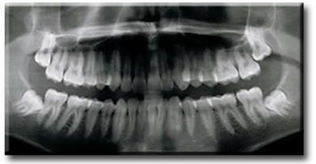

Panoramik Film

Periapikal Film